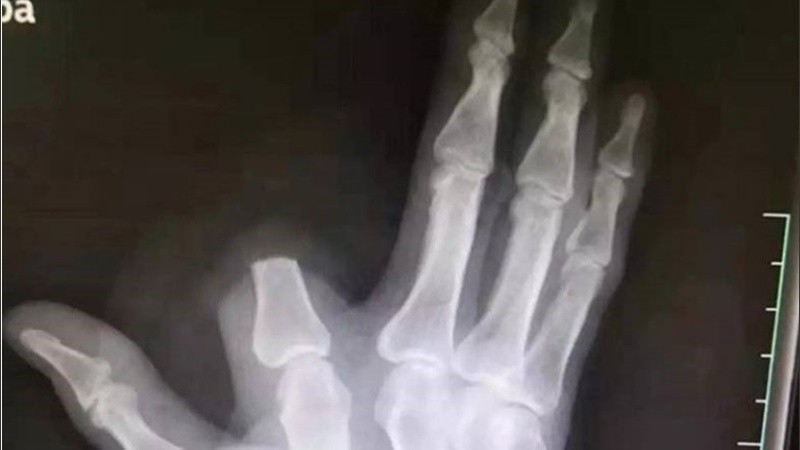

Según publicó ActualidadRT, el hombre sin dudarlo y para evitar que el veneno se propagara por su organismo, se cercenó su dedo índice separando la parte donde fue mordido del resto de la mano. Acto seguido, envolvió la herida y se dirigió al hospital más cercano, ubicado a 80 kilómetros de distancia en la ciudad de Hangzhou.

Zhang fue tratado por sus heridas y se encuentra recuperándose en su casa, aunque lamentablemente no pudo recuperar su dedo, ya que al apresurarse a al hospital se olvidó de recoger la extremidad amputada en la montaña.